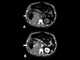

Retroperitoneal hemorrhage

Retroperitoneal bleeding is an accumulation of blood in the retroperitoneal space. Signs and symptoms may include abdominal or upper leg pain, hematuria, and shock. [Source: Wikipedia ]